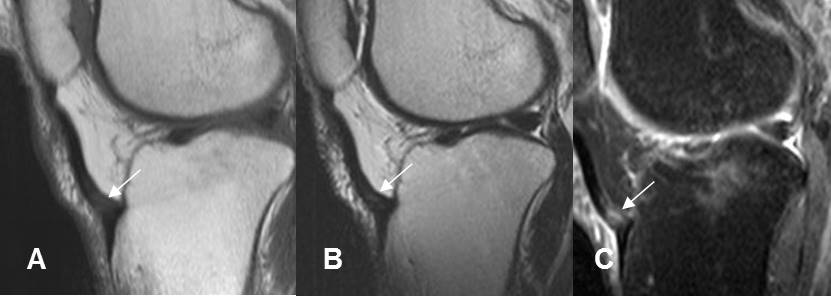

Fig 207. Rodilla del saltador.

A: RM sagital en T1, B: RM sagital en T2 y C: RM sagital en STIR. Cambios inflamatorios agudos en la inserción del tendón patelar el cual es hipointenso en T1 e hiperintenso en T2 y STIR, por inflamación aguda.